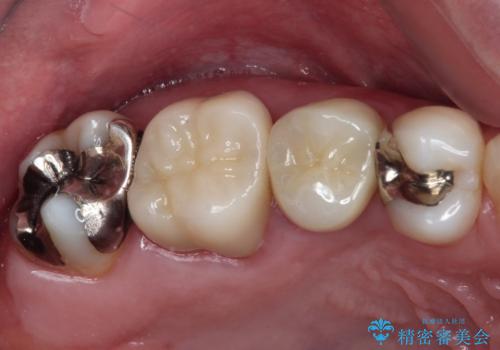

不快感が続く奥歯 外科処置を併用したセラミック補綴治療

奥歯が痛い セラミッククラウンでの虫歯治療